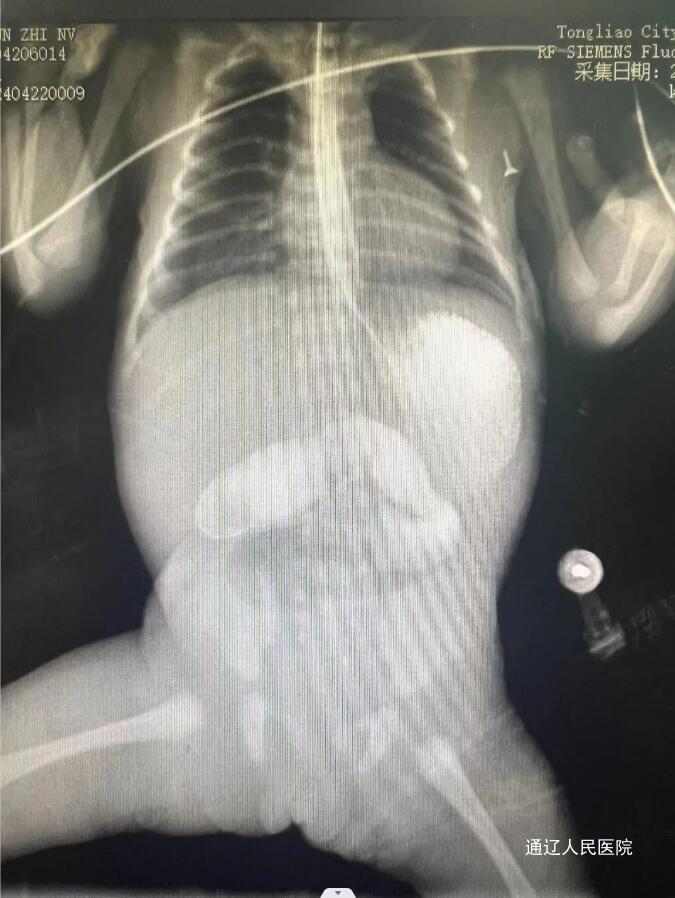

经术前检查与科室讨论后诊断为空肠闭锁,于当日上午行手术治疗。该术例难点在于患儿为孕34周早产儿,低出生体重儿(1500-2499g),伴心脑肺等各重要脏器发育不全,且肠管闭锁近端及远端粗细相差较大等多项不利因素,属四级手术,风险系数极高。

手术由小儿外科主任医师宋希春,主治医师杭盖协术前麻醉副主任高飞等几位医师共同完成。术中明确为肠闭锁Ⅰ型,膜式闭锁,行空肠隔膜切除术。空肠缝合为粘膜下单层缝合,避免内翻过多导致狭窄,术后立即转入新生儿病房李宏颖医护团队进行后续治疗,现已康复出院。本次手术的成功实施得益于我院多学科团队的协力配合。我院小儿外科在麻醉科及新生儿科的共同协作下常规开展新生儿手术案例不胜枚举,例如新生儿先天性肥厚性幽门狭窄,新生儿胃穿孔,新生儿坏死性小肠结肠炎,新生儿高位肛门闭锁,新生儿肠旋转不良等各类新生儿手术。该病例属中国出生缺陷干预救助基金会结构畸形救助病种之一,经医保报销后仍享有结构畸形救助。我院为中国出生缺陷干预救助基金会通辽地区唯一定点实施机构,将竭诚为广大市民服务。